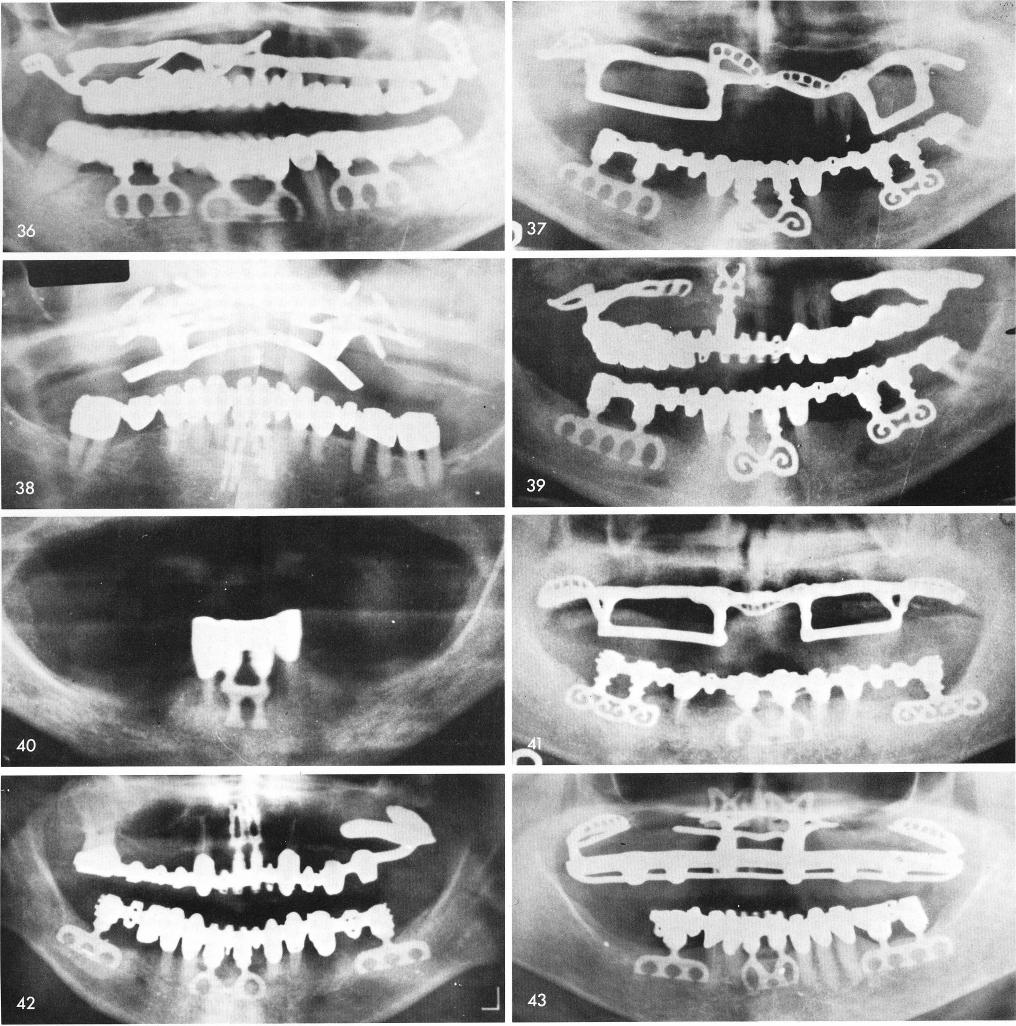

Fig. 36 through 45 shows x-rays of other mid-line cases.

1 X rays of mandibular midline cases for implants